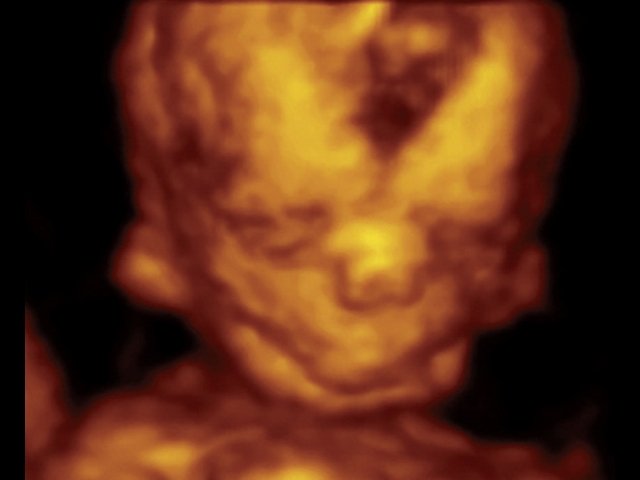

При ультразвуковом исследовании выявлены множественные особенности лицевого фенотипа у плода: микрогнатия (рис. 2–4), треугольная форма лица (рис. 5), опущенные книзу глазницы и гипоплазия скуловых дуг (рис. 6, 7), аномальная форма и положение ушей (рис. 5, 7).

Рис. 4. Микрогнатия - 3D-реконструкция лица плода при синдроме Тричера Коллинза.

Рис. 7. Фенотип лица плода с синдромом Тричера Коллинза.